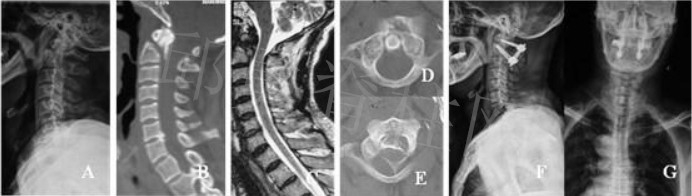

#5825 男,41岁,腰1压缩性骨折。X线正侧位片显示L1压缩性骨折(FigureA,B)。横断面CT清晰骨折块向后方移位,脊髓受压(Figure C)。患者接受后路L1骨折切开复位AF固定融合术(Figure D,E)。

#5843 男,21岁,腰3爆裂性骨折合并不全瘫。X线正侧位片显示L3压缩性骨折(Figure A,B)。横断面CT清晰骨折块向后方移位,脊髓受压(Figure C)。患者接受后路L3全椎板切除减压AF固定融合术(Figure D,E)。